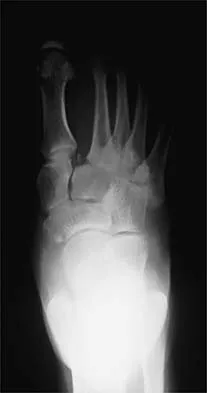

The oblique radiograph of the foot and the CT scan shown in Figures 10a and 10b show a patient whose symptoms have failed to respond to rest and non-steroidal anti-inflammatory drugs. What is the best course of action?

Explanation

The radiograph and MRI scan show elongation and fragmentation of the os peroneum. Although casting, orthoses, and steroid injection may relieve symptoms, excision of the os peroneum and primary repair when necessary, with or without tenodesis of the peroneus longus to the peroneus brevis, have been shown to produce excellent results. Haddad SL: Disorders of tendons: Peroneal tendon dysfunction, in Coughlin MJ, Mann RA (eds): Surgery of the Foot and Ankle, ed 7. St Louis, MO, Mosby, 1999, pp 812-817.